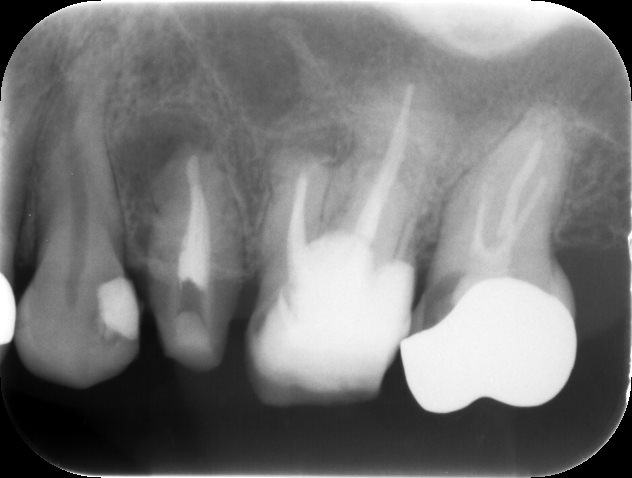

根の治療完了時レントゲン

根管治療が完了しました。レントゲン上では術前と差がありませんが、噛む時の痛みなどの症状は消失していました。